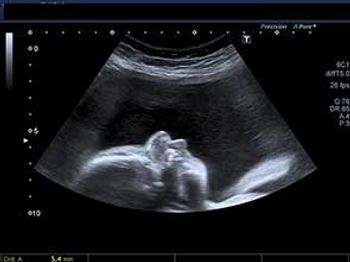

What's your diagnosis based on these images of the fetal neck?